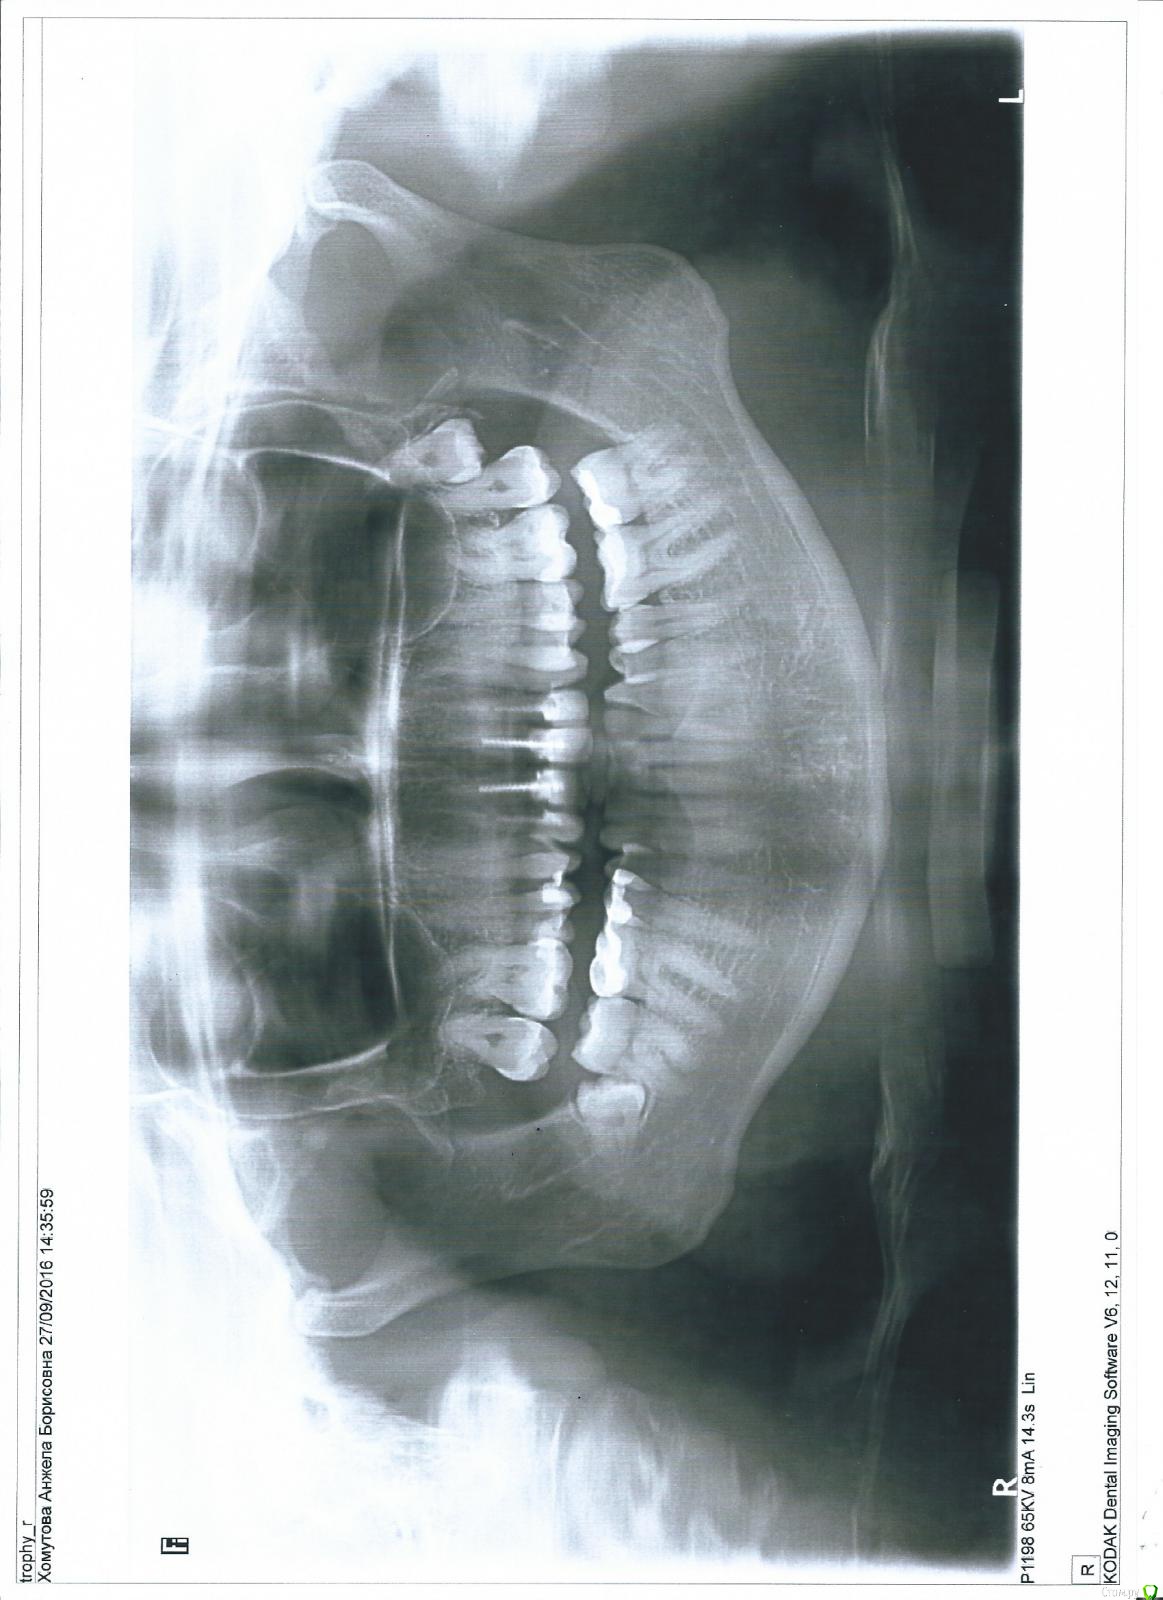

Jacqui Опубликовано 27 сентября, 2016 Поделиться Опубликовано 27 сентября, 2016 Здравствуйте, уважаемые врачи. Очень прошу вашего мнения. На консультации по поводу протезирования верхних резцов (от клыка до клыка) мне сказали, что коронки ставить некуда, только удалять корни. Сейчас у меня эти зубы отреставрированы композитным материалом. Действительно ли прав врач? Очень прошу откликнуться. Спасибо. Ссылка на комментарий

DmitrySH Опубликовано 27 сентября, 2016 Поделиться Опубликовано 27 сентября, 2016 По данному снимку сложно оценить степень разрушения корней. Нужен визуальный осмотр. Для принятия решения может потребоваться удаление всех этих пломб. 1 Ссылка на комментарий